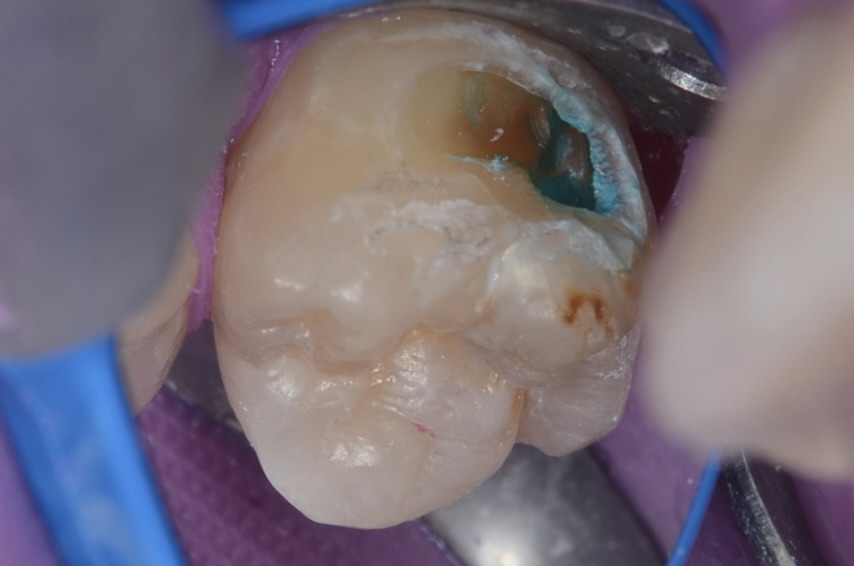

20代 虫歯治療 VPT(歯髄温存療法)ダイレクトボンディング #36

Before

After

| 年齢 | 20代 | 治療方法 | VPT(歯髄温存療法)/ダイレクトボンディング |

|---|---|---|---|

| 性別 | 女性 | 通院回数 | 2回 |

| 主訴 | むし歯を治したい /神経を取りたくない/できるだけ神経を取りたくない | 費用 | 170,500円(税込) |

| 治療のメリット | 神経を保存できる。歯を削る量を少なくできる。自然な形にできる | ||

| 治療のデメリット | 神経を保存できない場合がある。 | ||